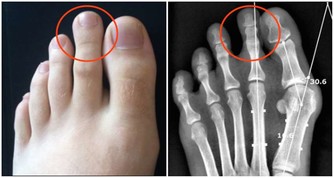

9 山莨菪鹼:掩蓋症狀,長期使用有風險

由於山莨菪鹼能夠解除平滑肌痙攣,在胃腸絞痛的時候常常被使用。此外,還用於腦血栓、腦栓塞等。

這種藥物年老體虛的老年朋友要謹慎使用,尤其是前列腺肥大的老年男性。由於此種藥物作用於平滑肌,使用此藥後容易導致前列腺充血甚至引發尿瀦留。

這是一種對症治療的藥物,能夠緩解症狀,但無法根治。正因為此,它同布洛芬一樣,也會掩蓋疼痛真正的病因,需要慎用,同時避免長期使用。

這個藥物有很多副作用,其中一種就是口乾,這主要是由於藥物抑制了唾液腺的分泌。遇到這種情況時,可以通過服用酸梅、多飲水來緩解症狀。

還有一些副作用包括面紅、輕度擴瞳、視近物模糊等,遇到這些副作用時不要過度擔心,一般在停藥1-3小時後能夠漸漸消失。